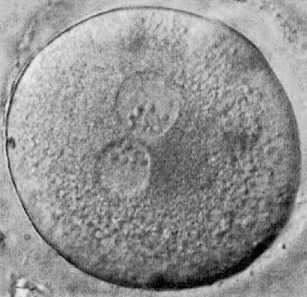

En dicha ley se prohíbe expresamente la constitución de preembriones o embriones humanos exclusivamente con fines de experimentación y aprueba la clonación terapéutica, que consiste en la transferencia del núcleo de una célula a un ovocito al que se le ha extraído su núcleo para reprogramar su crecimiento celular y poder crear así células madre embrionarias capaces de crear tejidos u órganos que se puedan trasplantar a la persona enferma.